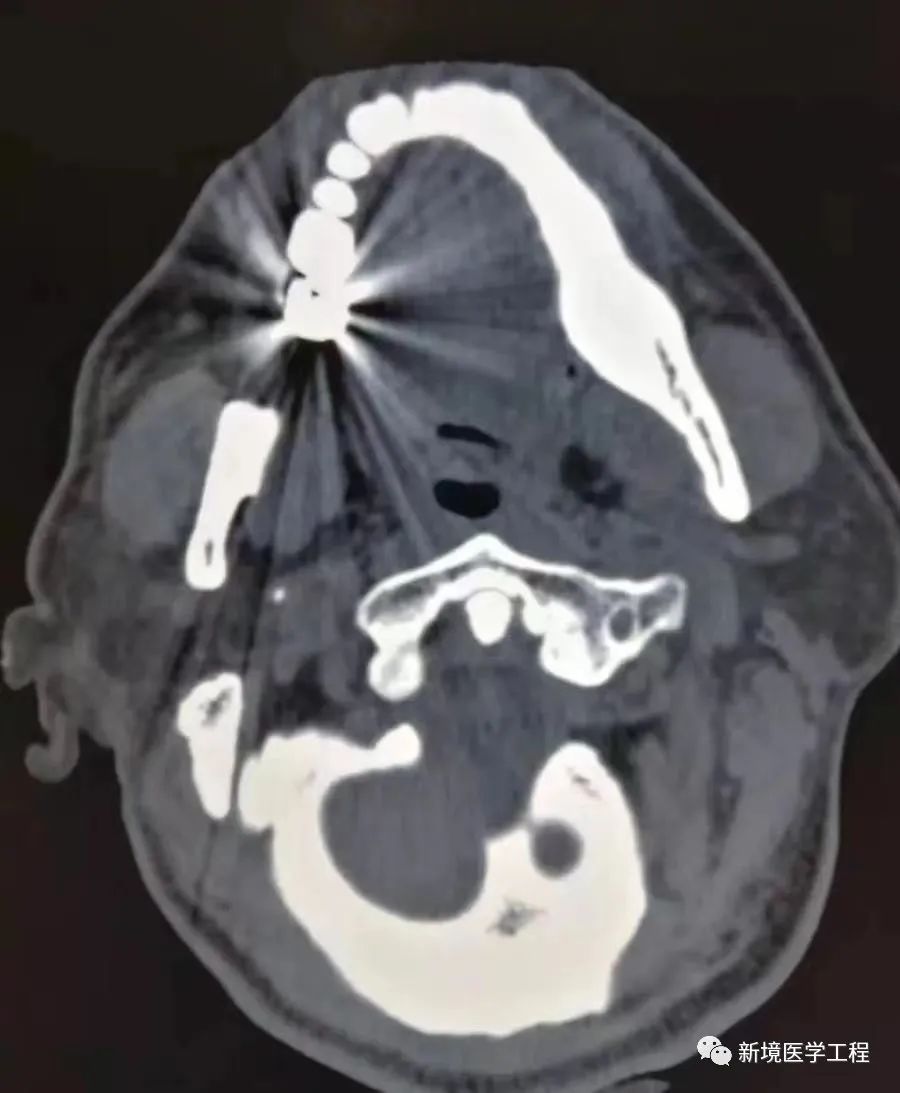

2.3「体内金属伪影」

【产生原因】

患者体内有金属,因为金属吸收了X射线,导致投影数据产生不完全,部分数据丢失导致放射状伪影。

【解决办法】

-

移除金属物体(如可行)

-

使用去金属伪影的算法,如MAC等